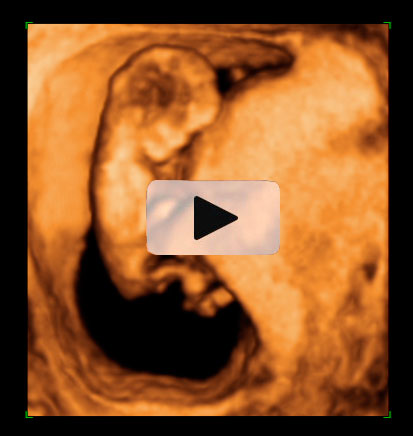

Ecografía 4D de la semana 12: Feto moviéndose de perfil

La ecografía 4D muestra al bebé moviéndose a sus anchas en el útero materno. Este plano de perfil muestra brazos, piernas y cordón umbilical en movimiento constante, lo que es es signo de vitalidad fetal. Las estructuras básicas de un feto de 12 semanas de gestación se parecen mucho a las de un bebé recién nacido; es ya todo un niño, aunque le falten unos seis meses aproximadamente para ver la luz.

Ecografía 4D: feto de 12 semanas moviéndose de perfil